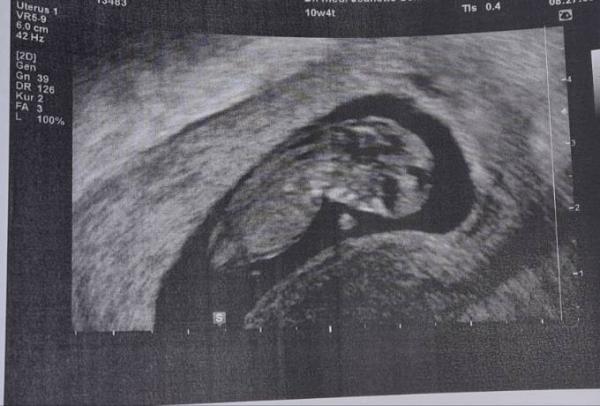

Hallo Mädels, ich komme gerade vom FA Termin und bin mega glücklich Dem Krümel gehts hervorragend... und ich hatte schon Panik weil ich seit Tagen keine Symptome mehr hatte. Aber alles gut Verrückt was man alles gesehen hat. Jetzt kann Weihnachten kommen

Bild zu Über Glücklich - Forum für Juli - Mamis